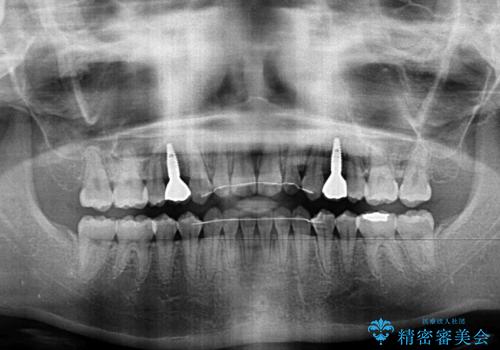

- 歯の欠損による隙間だらけの歯並びを気にして来院された患者様です。

上顎左右1本ずつ欠損していたため、歯列矯正により欠損部位にスペースを集め、その後欠損部位をインプラントにて補綴することとしました。

インビザラインによる矯正治療も提案しましたが、長時間の装着や自己管理が難しいとお考えで、ワイヤーによる矯正治療を行いました。

歯並びは比較的早めに整いましたが、インプラントを埋入するにあたって前後の歯根位置を改善する必要があり、矯正治療に期間を要することとなりました。